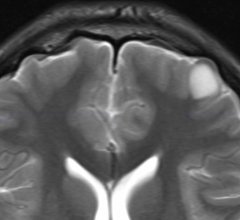

At least a few Europeans think ventilation MRI should be commonplace.